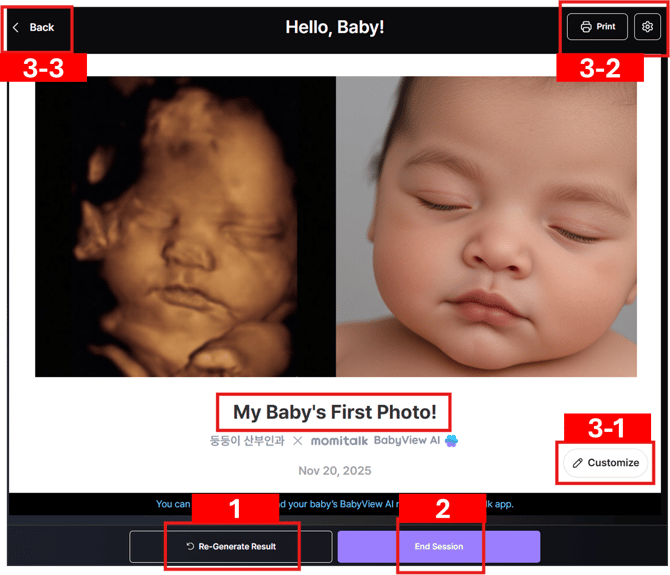

Reviewing and Finalizing Your BabyView AI Result

Once the AI image is generated, you’ll see the result screen as shown below:

From here, you can review, re-generate, or finalize your result before completing the session.

1. End Session

- Click “End Session” if you’re satisfied with the result.

- Once the session is ended:

- The BabyView AI image is finalized and automatically uploaded to the Bomee app for the customer to view.

- The session is considered complete and no further changes can be made.

2. Re-Generate Result

- Click “Re-Generate Result” if you’d like to create a new version of the image.

- You can re-generate multiple times within the same session at no additional cost.

- When you re-generate:

- The previous AI image will be replaced by the newly generated one.

- The process will run again (takes another 1–3 minutes).

- You’ll be shown two versions side-by-side for comparison and can select your preferred one.

- When you click “Re-Generate Result,” a short feedback window will appear asking why you want to re-generate.

→ Please answer carefully — this feedback helps us continuously improve BabyView AI’s accuracy and quality.

Note: Re-generation is available only before you end the session. Once End Session is clicked, the current image is locked, and any further generation after "ended session" will be considered a new, billable session.

3. Additional Options

3-1. "Customize" Message

- Click “Customize” to change the text caption below the photo.

- The default caption is “My Baby’s First Photo!”

- You can freely edit it (e.g., “Welcome Baby Emma!”).

3-2. Print

- Click “Print” to print the image directly from your connected printer.

- By default, both the ultrasound photo and the BabyView AI image will print side-by-side.

- To print only the BabyView AI image, click the gear (⚙️) icon next to the Print button and select your preference.

3-3. "Back" to change original ultrasound image

- Click “Back” to return to the image selection screen if you want to use a different ultrasound image.

- Note that going back will delete the previously generated AI image for this session.